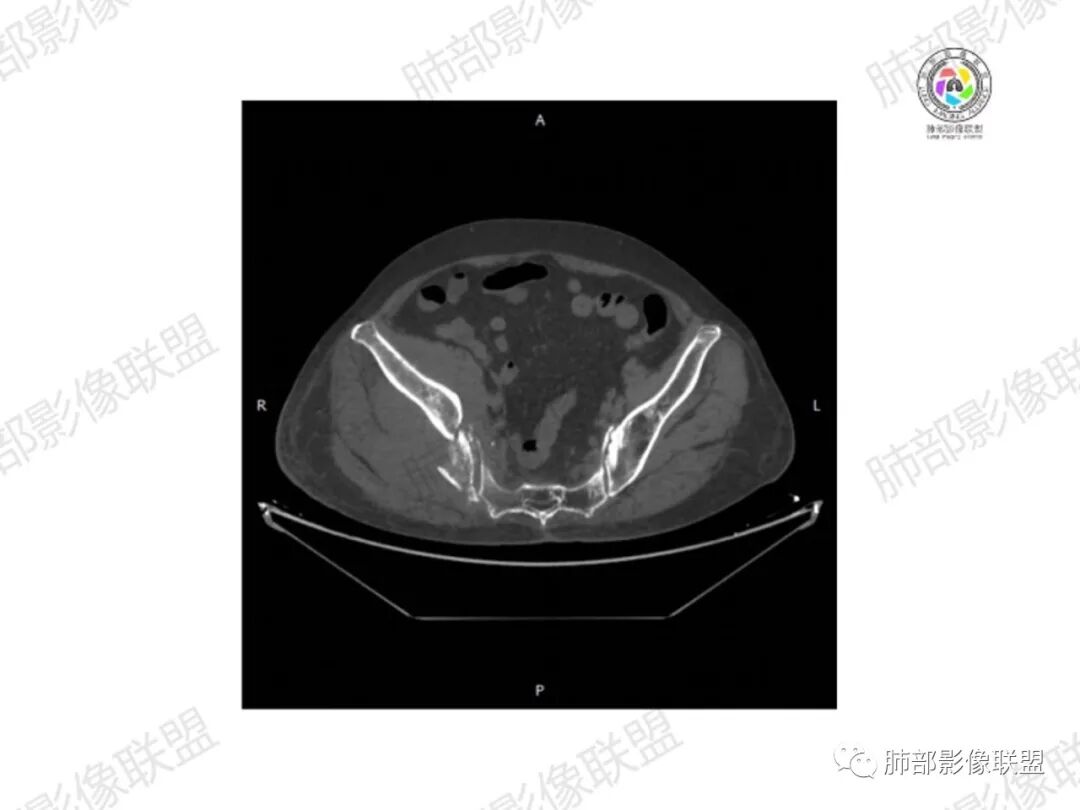

1.老年女性,直肠癌术后放疗后5年,右臀部疼痛4个月,加重半月

2.右髂骨轻度变形伴广泛骨质吸收破坏,边界不清且突破骨皮质。近中线区以溶骨性破坏为主,髂骨翼一侧则成骨性改变明显,骨表面见垂直骨针或花边样高密度瘤骨。

3.患骨多处皮质断裂,符合病理性骨折。注意折端可能会形成骨痂,但本例无论是形态还是部位都不符合骨痂。

4.患骨两旁(即盆骨内外)见边界不清的较大范围软组织快影,其间偶见骨化影。

1.边界不清的骨质吸收破坏,溶骨明显,骨皮质突破,软组织肿块,种种迹象表明其恶性无疑!

2.但注意这是有“成骨”的恶性骨肿瘤!我们知道老年患者的骨原发性恶性肿瘤“成骨”非常少见。少数转移瘤可为成骨型或混合型,女性患者如乳腺癌骨转移等。在男性,最典型的成骨转移是前列腺癌。

本例右侧髂骨具有较为典型的“骨肉瘤”影像学特征,有边界不清的吸收破坏、有新生骨、形成软组织肿块等等。